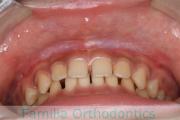

犬歯が八の字になっているので何とかしてほしいということで来院されました。上顎犬歯が左右とも前歯の方に向いていて、一期治療でまずは萌出誘導を行いました。

二期治療は、出っ歯の要素が強かったため、上顎のみ第二小臼歯を抜歯しています。

二期治療は2年強、25回程度の通院が必要でした。犬歯の埋伏歯は、うまく出すことができない場合があったり、出す際に周囲の歯の歯根に傷をつけるリスクがあったりします。

上顎

下顎

前歯の関係など

右側

正面

左側